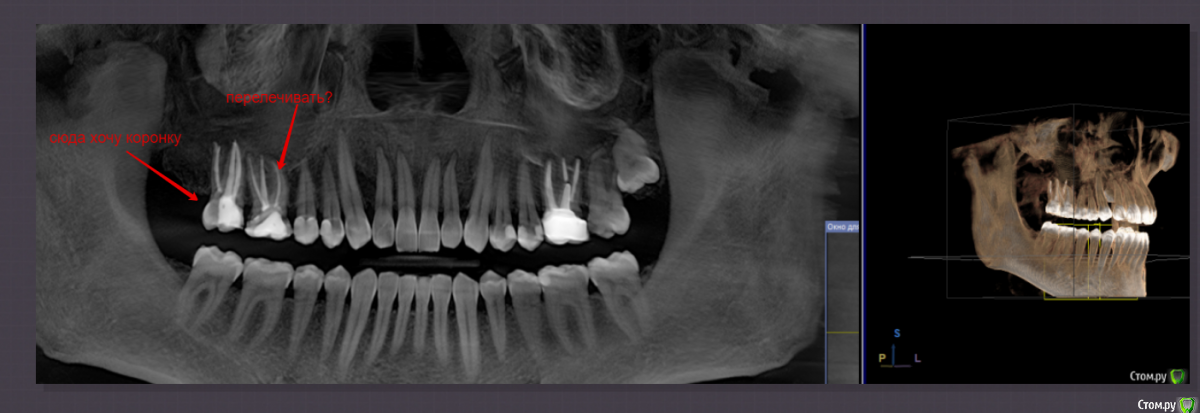

shamman Опубликовано 17 сентября, 2018 Поделиться Опубликовано 17 сентября, 2018 Добрый день, вопрос в следующем.Год назад перелечили каналы зуба.Рядом ещё один зуб, в котором по словам терапевта надо тоже каналы перелечивать. И типа идеальная схема: перелиываем второй зуб и сразу ставим 2 коронки.Как вы понимаете, с точки зрения расходов: перелечивание каналов 1 зуб + коронка 1 + коронка 2 = сразу существенная сумма.Врачу несколько раз задавал вопрос: "Можно ли сначала поставить коронку на 1 зуб, потом уже перелечить второй и поставить на него?".Каждый раз отвечала по-разному, и вразумительного ничего не понял. Подскажите, с точки зрения протезирования:- можно ли поставить на 1 зуб?- насколько велики риски если поставить на 1 зуб? с учётом того, что рядом стоящий будет позже переличиваться.- или таки копить деньги и делать всё раз? Из проблем сейчас, у того зуба куда хочу уже поставить, большой межзубный промежуток, на этой стороне из-за этого некмофортно жевать. Т.е. коронка сейчас уже бы существенно улучшила качество жизни. Снимок приложил, недавно сделал КТ.Если надо в др. ракурсах, могу приложить др. срезы.Заранее спасибо. Ссылка на комментарий

red_butler Опубликовано 17 сентября, 2018 Поделиться Опубликовано 17 сентября, 2018 на представленном снимке не увидел показаний к перелечиванию Ссылка на комментарий

shamman Опубликовано 18 сентября, 2018 Автор Поделиться Опубликовано 18 сентября, 2018 на представленном снимке не увидел показаний к перелечиванию1.Поэтому по поводу этого зуба решил не торопиться.2.Может сделать какое-то увеличение, чтобы получше рассмотреть? Ссылка на комментарий

red_butler Опубликовано 18 сентября, 2018 Поделиться Опубликовано 18 сентября, 2018 1.Поэтому по поводу этого зуба решил не торопиться.2.Может сделать какое-то увеличение, чтобы получше рассмотреть?покажите срезы Кт в области этого зуба Ссылка на комментарий

shamman Опубликовано 23 сентября, 2018 Автор Поделиться Опубликовано 23 сентября, 2018 покажите срезы Кт в области этого зубаВот приложил второй скрин, если по нему можно что-то сказать. Ссылка на комментарий

red_butler Опубликовано 23 сентября, 2018 Поделиться Опубликовано 23 сентября, 2018 есть периодонтит, перелечивайте Ссылка на комментарий